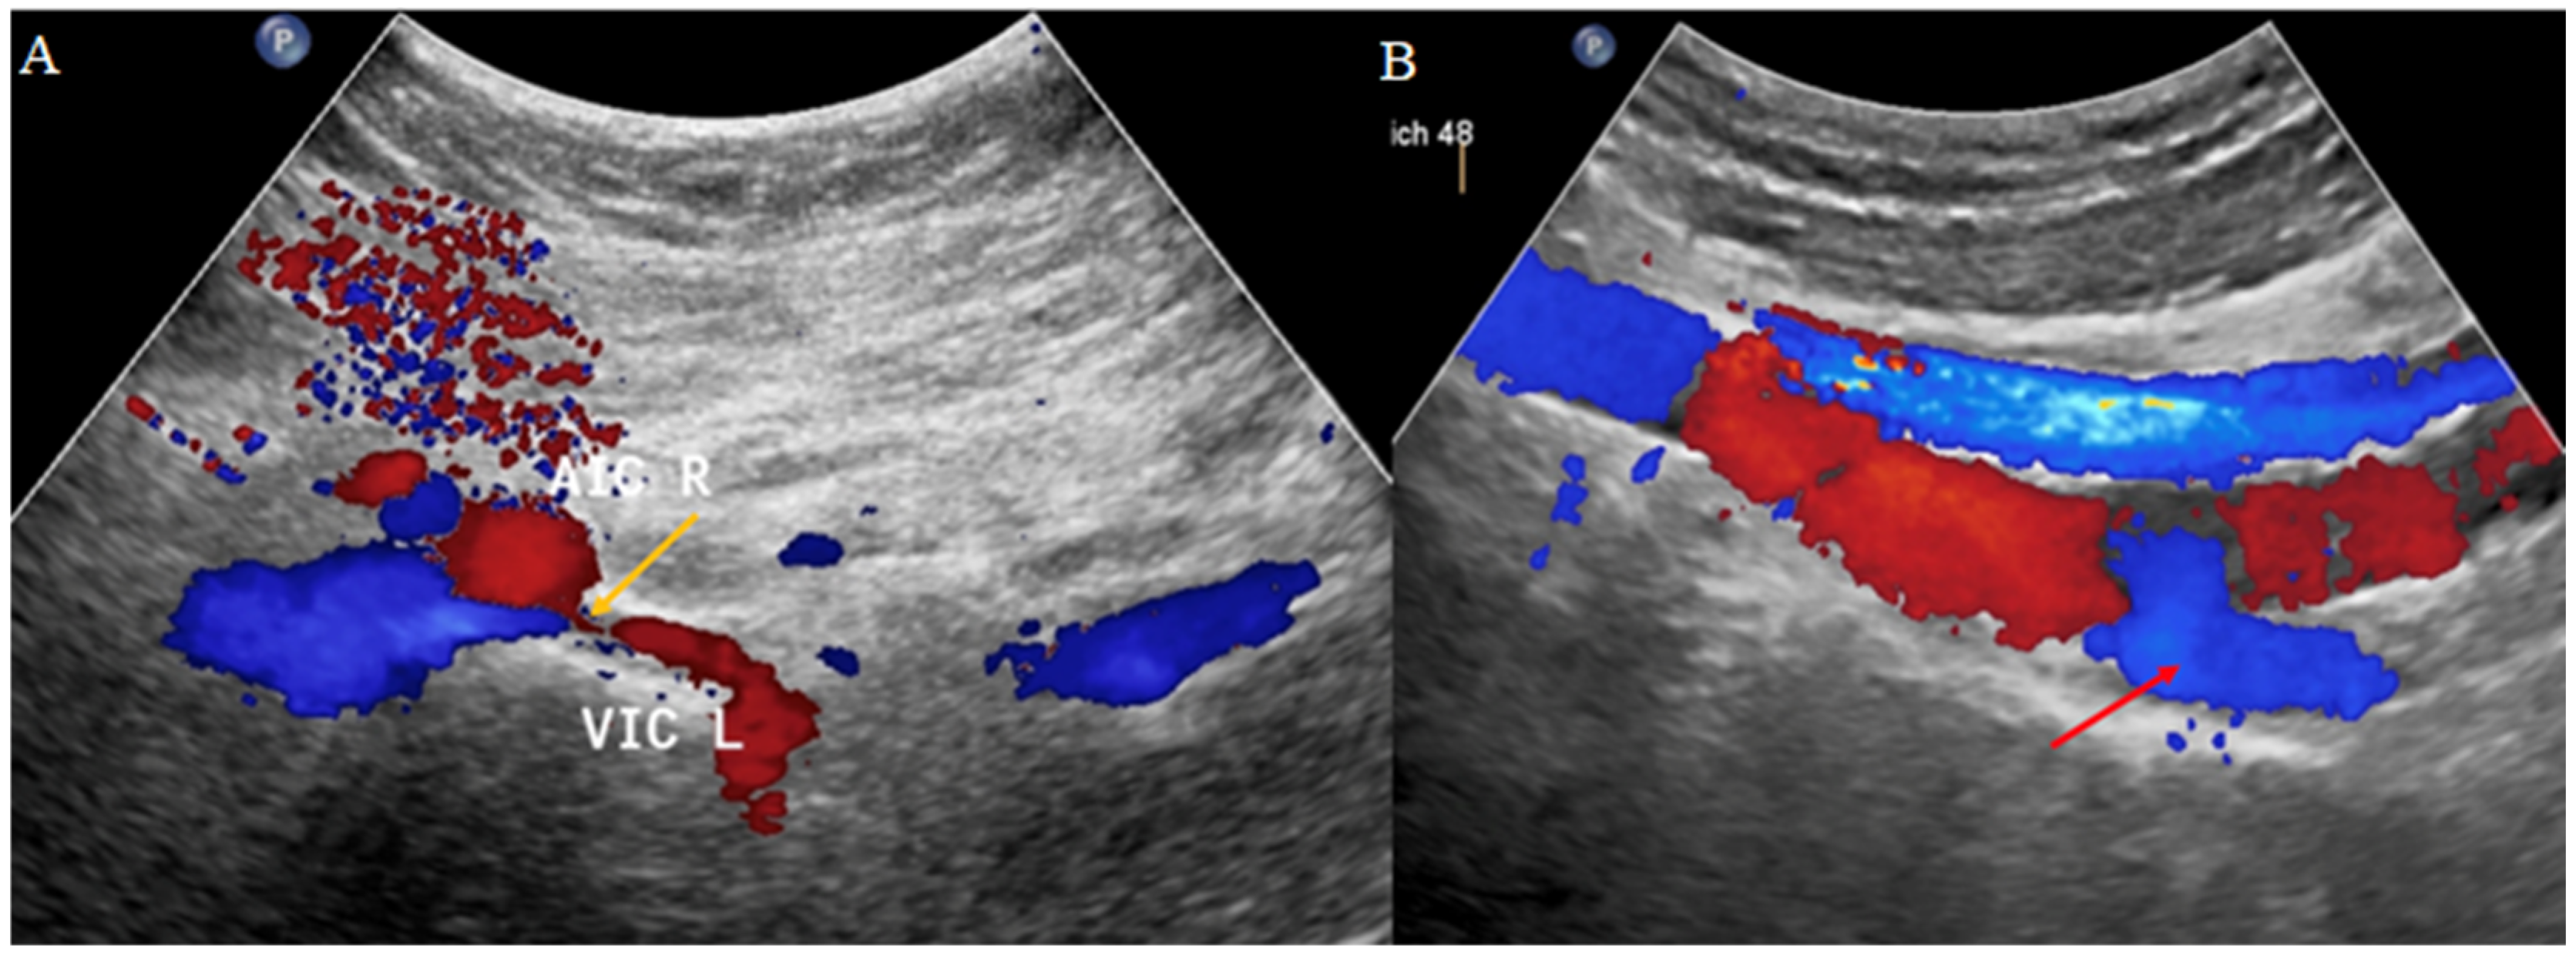

2.2.2. Transabdominal Ultrasonography